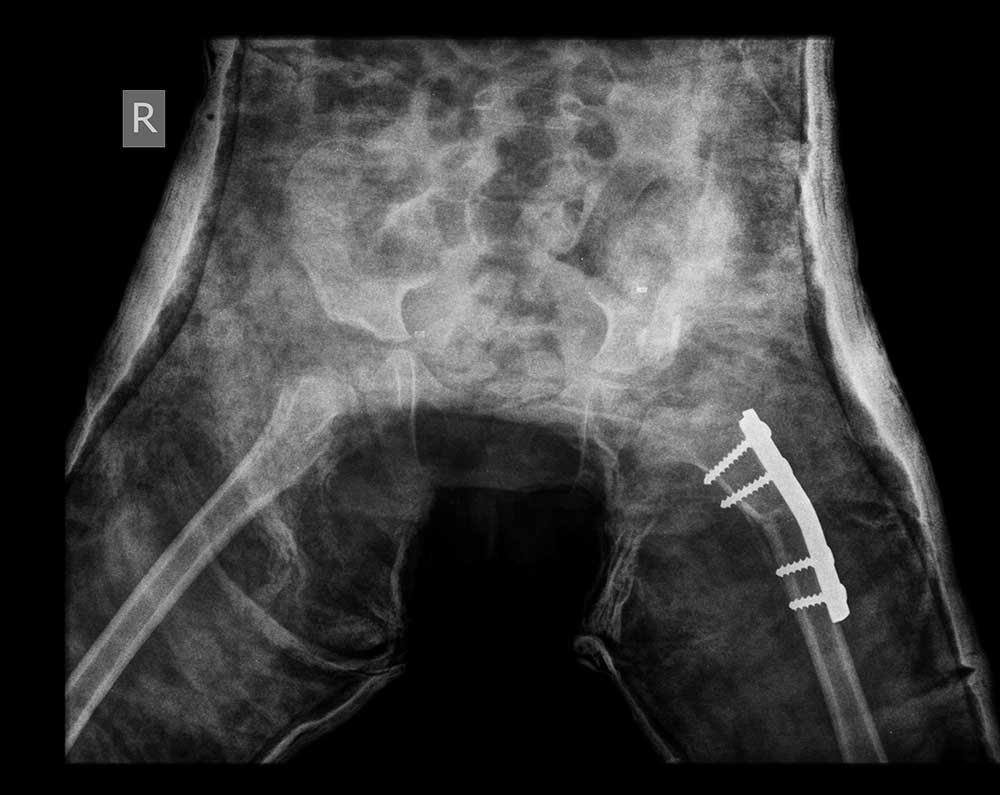

After surgery

Two years After surgery